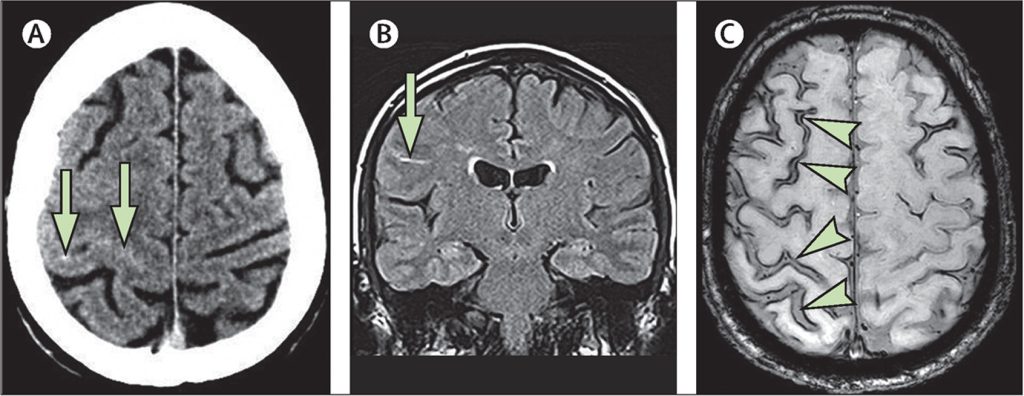

Η καλύτερη μέθοδος για τη διάγνωση της υπαραχνοειδούς αιμορραγίας είναι η αξονική τομογραφία χωρίς σκιαγραφικό του εγκεφάλου. Αυτή έχει υψηλή ευαισθησία και θα εκτιμήσει σωστά πάνω από το 95 τοις εκατό των περιπτώσεων-ιδιαίτερα κατά την πρώτη ημέρα μετά την έναρξη της αιμορραγίας.

Η Μαγνητική τομογραφία μπορεί να είναι πιο ευαίσθητη από την αξονική τομογραφία μετά από αρκετές ημέρες. Μέσα σε έξι ώρες από την έναρξη των συμπτωμάτων η αξονική τομογραφία είναι 100 τοις εκατό ευαίσθητη.

Η αγγειογραφία. Αν η υπαραχνοειδής αιμορραγία επιβεβαιωθεί, η προέλευσή της πρέπει να προσδιορίζεται. Εάν η αιμορραγία οφείλεται σε ανεύρυσμα γίνεται εγκεφαλική αγγειογραφία και αξονική αγγειογραφία.